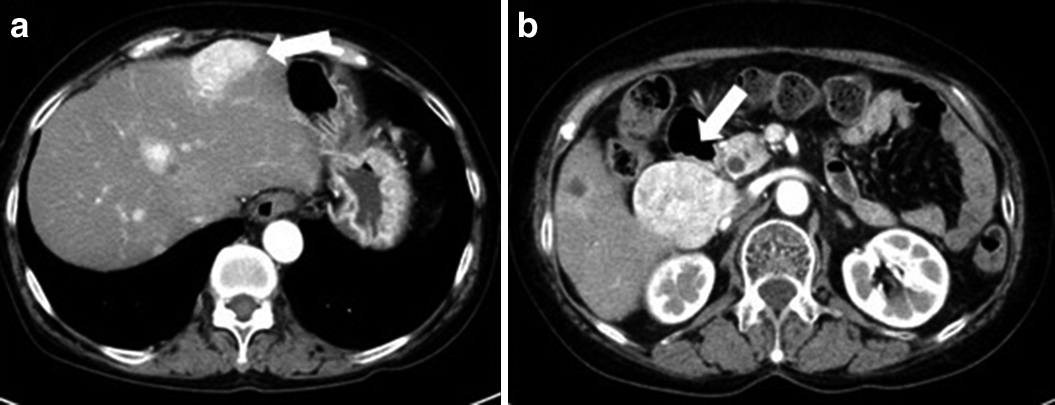

2012年12月,多発肝転移が出現したため(Fig. 2),エベロリムス10 mg/dayの内服を開始したが,2015年に間質性肺炎が出現したため中止した.2013年10月からエベロリムスに併用してTACEを2016年10月まで3年にわたって3~6か月毎に計10回施行した.

Abdominal dynamic CT showed highly-enhanced multiple metastatic liver tumors in the early phase (arrows) (a, b).

2016年11月,CTにて左胃動脈,腹部大動脈周囲リンパ節転移が出現したため,2017年3月からスニチニブ25 mg/dayの内服を開始した.2017年5月,内服開始後2か月の腹部造影CTにて,多発肝転移出現時より指摘されていた約20か所の肝転移巣は大きさや個数に変化を認めなかったが,腫瘍の早期濃染像が多血性から乏血性に変化しており治療効果ありと判断した(Fig. 3).CTから16日後に,外出先で腹痛,気分不良,嘔気にて動けなくなり,ショック状態となって当院へ救急搬送された.

Abdominal dynamic CT showed that multiple metastatic liver tumors did not change in size but exhibited lowly enhanced changes in the early phase (arrows) (a, b).